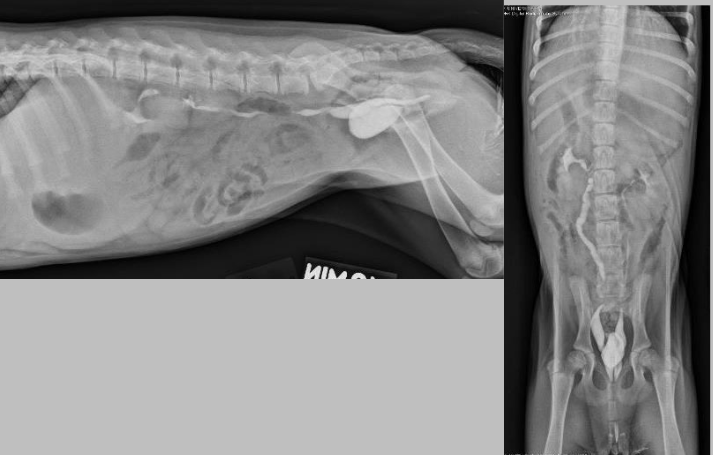

what is going on here?

you can see tubular soft tissue opacities along the caudal lateral body wall and loss of serosal detail caudally, this is pyometra